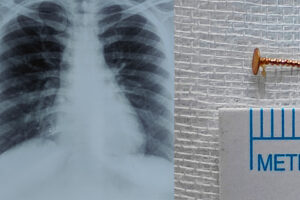

konnivartha.com: കൊച്ചി മുണ്ടംവേലി സ്വദേശിനിയായ 44 വയസ്സുകാരിയുടെ ശ്വാസകോശത്തിൽ നിന്നാണ് കാണാതായ മൂക്കുത്തിയുടെ ഭാഗം പുറത്തെടുത്തത്. വിട്ടുമാറാത്ത പനിയും ചുമയുമായി കൊച്ചിയിലെ സ്വകാര്യ ആശുപത്രിയിൽ ചികിത്സ തേടിയപ്പോൾ എടുത്ത എക്സ്-റേയിലാണ് നാലുവർഷം മുൻപ് കാണാതായ മൂക്കുത്തിയുടെ ചങ്കിരി വലത്തെ ശ്വാസകോശത്തിന്റെ കീഴ്ഭാഗത്ത് തറച്ചിരിക്കുന്നതായി... Read more »